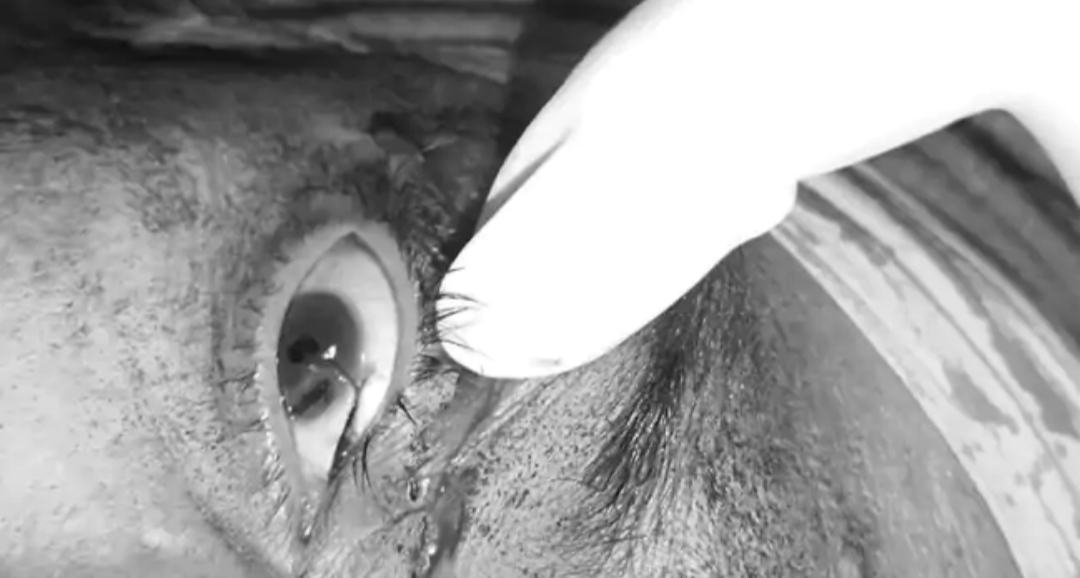

Punjab ujala news : फगवाड़ा के चाचोकी पुल के पास चाइना डोर की चपेट में आने से एक 50 वर्षीय व्यक्ति गंभीर रूप से जख्मी हो गया। डॉक्टरों ने उसे फगवाड़ा के सिविल अस्पताल से गंभीर हालत में निजी अस्पताल रेफर कर दिया है। घायल व्यक्ति की पहचान तरलोक सिंह निवासी गांव घुमना, फगवाड़ा के रूप में हुई है।मिली जानकारी के अनुसार तरलोक सिंह अपनी मोटरसाइकिल पर अपने गांव जा रहा था। जब वह चाचोकी पुल पर पहुंचा तो चाइना डोर की चपेट में आ गया। इससे उसकी आंख, नाक और मुंह के अन्य हिस्सों पर लंबा कट लग गया। घटना में पीड़ित के मुंह पर काफी गहरे घाव बने हैं। डोर से तरलोक की आंख की पुतली को भी क्षति पहुंची है।